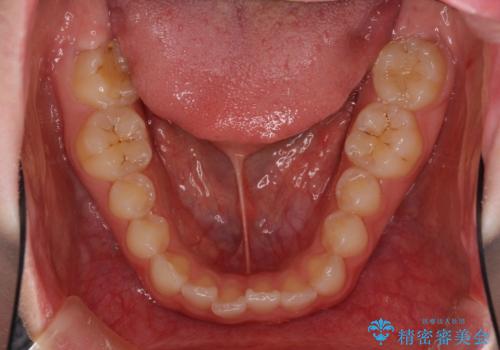

- 前歯の歯並びと虫歯を気にして来院された患者様です。

上下前歯の歯列不正はインビザラインにより歯列を整え、その後に、前歯5本をオールセラミッククラウンにて補綴治療することとしました。

矯正治療前に前歯のむし歯治療を行ったものの、樹脂で充填するには虫歯が広範囲であったため、審美的に問題がありました。